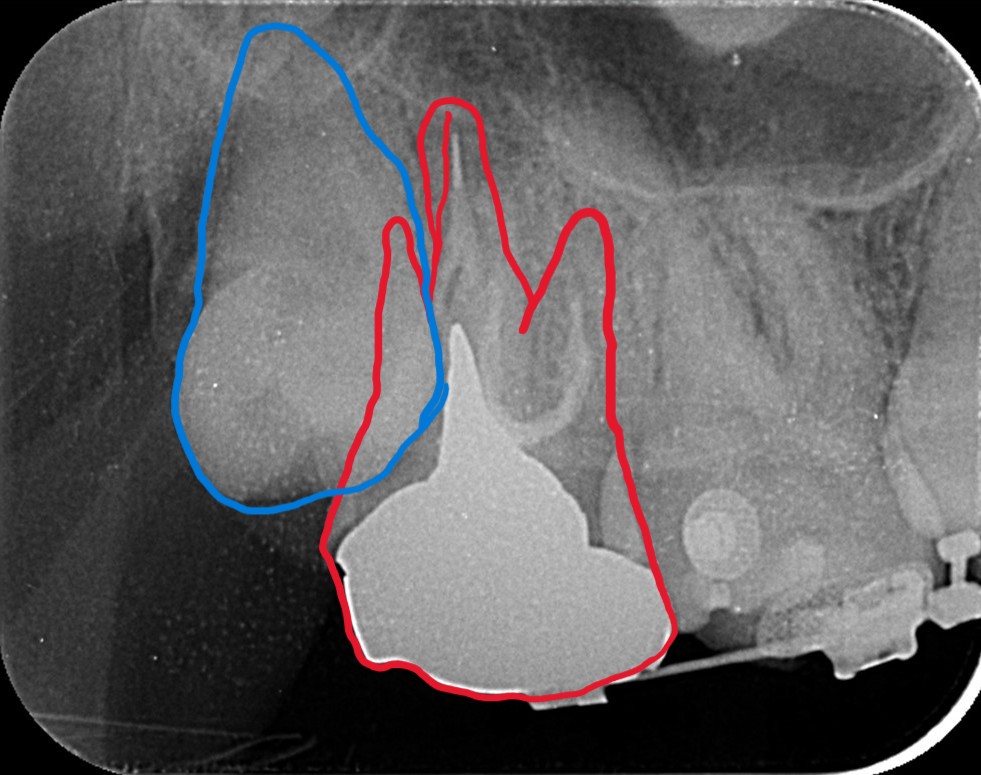

上の歯列を更に後方へ移動させるためには、右上の埋伏した智歯が邪魔でした。

しかし、その歯は神経を取り、内部を大きく削り残った歯質が薄くなり弱くなっています。

さらに言うと神経を取る治療にステップで治療器具を折れ込ませてしまったようです。

普通なら埋伏している智歯を抜歯するのですが、今回、手前の奥歯の条件が悪かったので、あえて手前の差し歯になっている奥歯(赤い線で囲われた歯)を抜歯して、埋っている智歯(青い線で囲われた歯)を残して、将来萌出してきて咬合に参加する未来を期待することになりました。